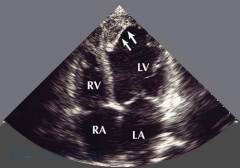

Эхокардиография

Эхокардиографию называют еще УЗИ сердца, так как для получения изображения здесь используют ультразвуковые волны. Данный метод обследования является наиболее информативным при кардиомиопатиях, так как он помогает увидеть камеры сердца и его стенки собственными глазами. Аппарат для ЭхоКГ может измерить толщину стенок, диаметр полостей, а в режиме «допплер» (допплерография) – и скорость кровотока. Именно на основании этого исследования обычно ставится окончательный диагноз.

При кардиомиопатиях на ЭхоКГ можно выявить следующие характерные нарушения:

• При дилатационной форме расширяется полость сердца без значительного утолщения стенок. Одновременно могут быть несколько увеличены другие камеры сердца. Клапаны при этом могут работать нормально. Фракция выброса крови снижается не менее чем на 30 – 35%. Могут появляться тромбы в расширенной полости.

• При гипертрофической форме выявляется утолщение стенки и ограничение ее подвижности. Полость камеры при этом зачастую уменьшается. У многих пациентов обнаруживают нарушения в работе клапанов. Кровь при сокращении левого желудочка частично забрасывается обратно в предсердие. Завихрения в кровотоке ведут к образованию тромбов.

• При рестриктивной форме обнаруживается утолщение эндокарда (в меньшей степени – миокарда) и уменьшение объема левого желудочка. Наблюдается нарушение наполнения полости кровью в диастолу. Нередко болезнь сопровождается недостаточностью митрального и трикуспидального клапанов.

• При специфических формах удается обнаружить очаг фиброза, нарушение клапанов, фиброзный перикардит или другие заболевания, которые привели к развитию кардиомиопатии.